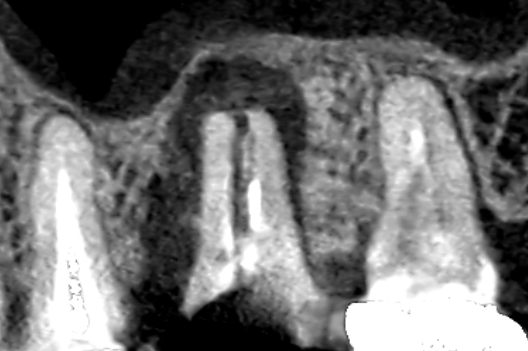

歯科用顕微鏡で根管内を確認したところ、歯根破折が認められなかったため、精密根管治療を行いました。赤い矢印の歯が精密根管治療を行った歯です。